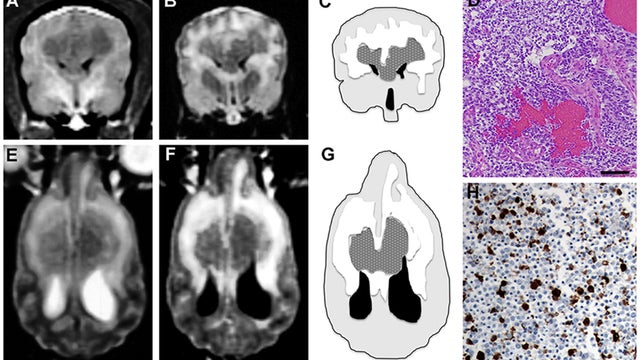

Johns Hopkins Sidney Kimmel Cancer Center was recently given funding to research a new experimental treatment on dogs who've been diagnosed with brain cancer -- in hopes that the treatment will ultimately save humans.

Glioblastoma is an aggressive form of cancer that occurs in the brain and spinal cord